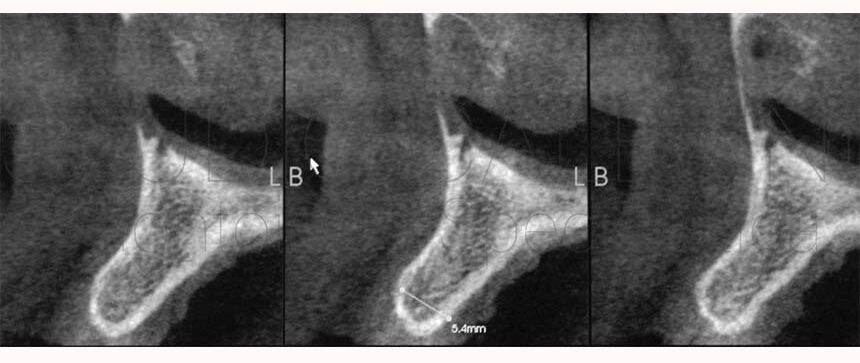

Nel presente articolo vi presentiamo una delle migliori soluzioni per risolvere l’agenesia bilaterale degli incisivi laterali superiori che, in questo caso, è associata a deficit osseo, cioè alla scarsa quantità di osso presente nel sito edentulo, ed alla marcata inclinazione della pre-maxilla (la parte anteriore del mascellare superiore).

- Deficit ossei in ambedue i siti che dovranno alloggiare gli impianti.

- Marcata inclinazione della premaxilla

- Nei siti in cui non è presente il dente permanente l’osso alveolare non è sviluppato.

- Il trattamento implantare richiede in questi casi l’applicazione di tecniche rigenerative che utilizzano membrane sintetiche, trapianti ossei o innesti di osso sintetico.

- L’approccio “Morphogenic Tissue Management” permette di ricostruire l’anatomia ideale ed ottenere sistematicamente un brillante risultato funzionale ed estetico stabile nel tempo in un’unica fase chirurgica, contestuale al posizionamento implantare, senza utilizzare membrane o trapianti di osso e contenendo moltissimo i costi economici, temporali, biologici e psicologici del trattamento implanto-protesico.